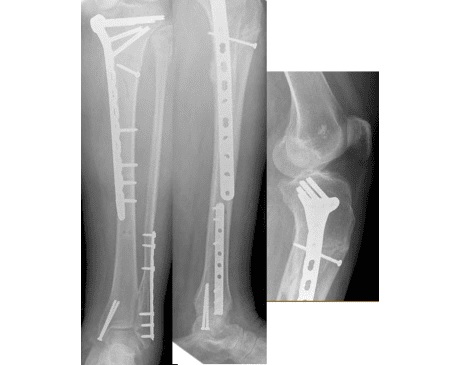

I was hit by car, had a compound fracture with a bone sticking out of my left foot. Broken tibia and fibia?. Screwed plate and bones back together. I am healing fine, next visit 3/26 to remove stiches. I seem to have total function of foot. Still have 2 more weeks of not using leg, but very hopeful.